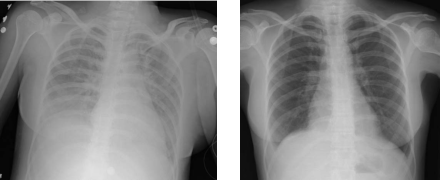

A chest x-ray of transfusion-related acute lung injury (left) which lead to ARDS. Right is a normal X-ray before the injury.

Diagnostic criteria for ARDS have changed over time as understanding of the pathophysiology has evolved. The international consensus criteria for ARDS were most recently updated in 2012 and are known as the "Berlin definition".[13][14] In addition to generally broadening the diagnostic thresholds, other notable changes from the prior 1994 consensus criteria[5] include discouraging the term "acute lung injury," and defining grades of ARDS severity according to degree of decrease in the oxygen content of the blood.